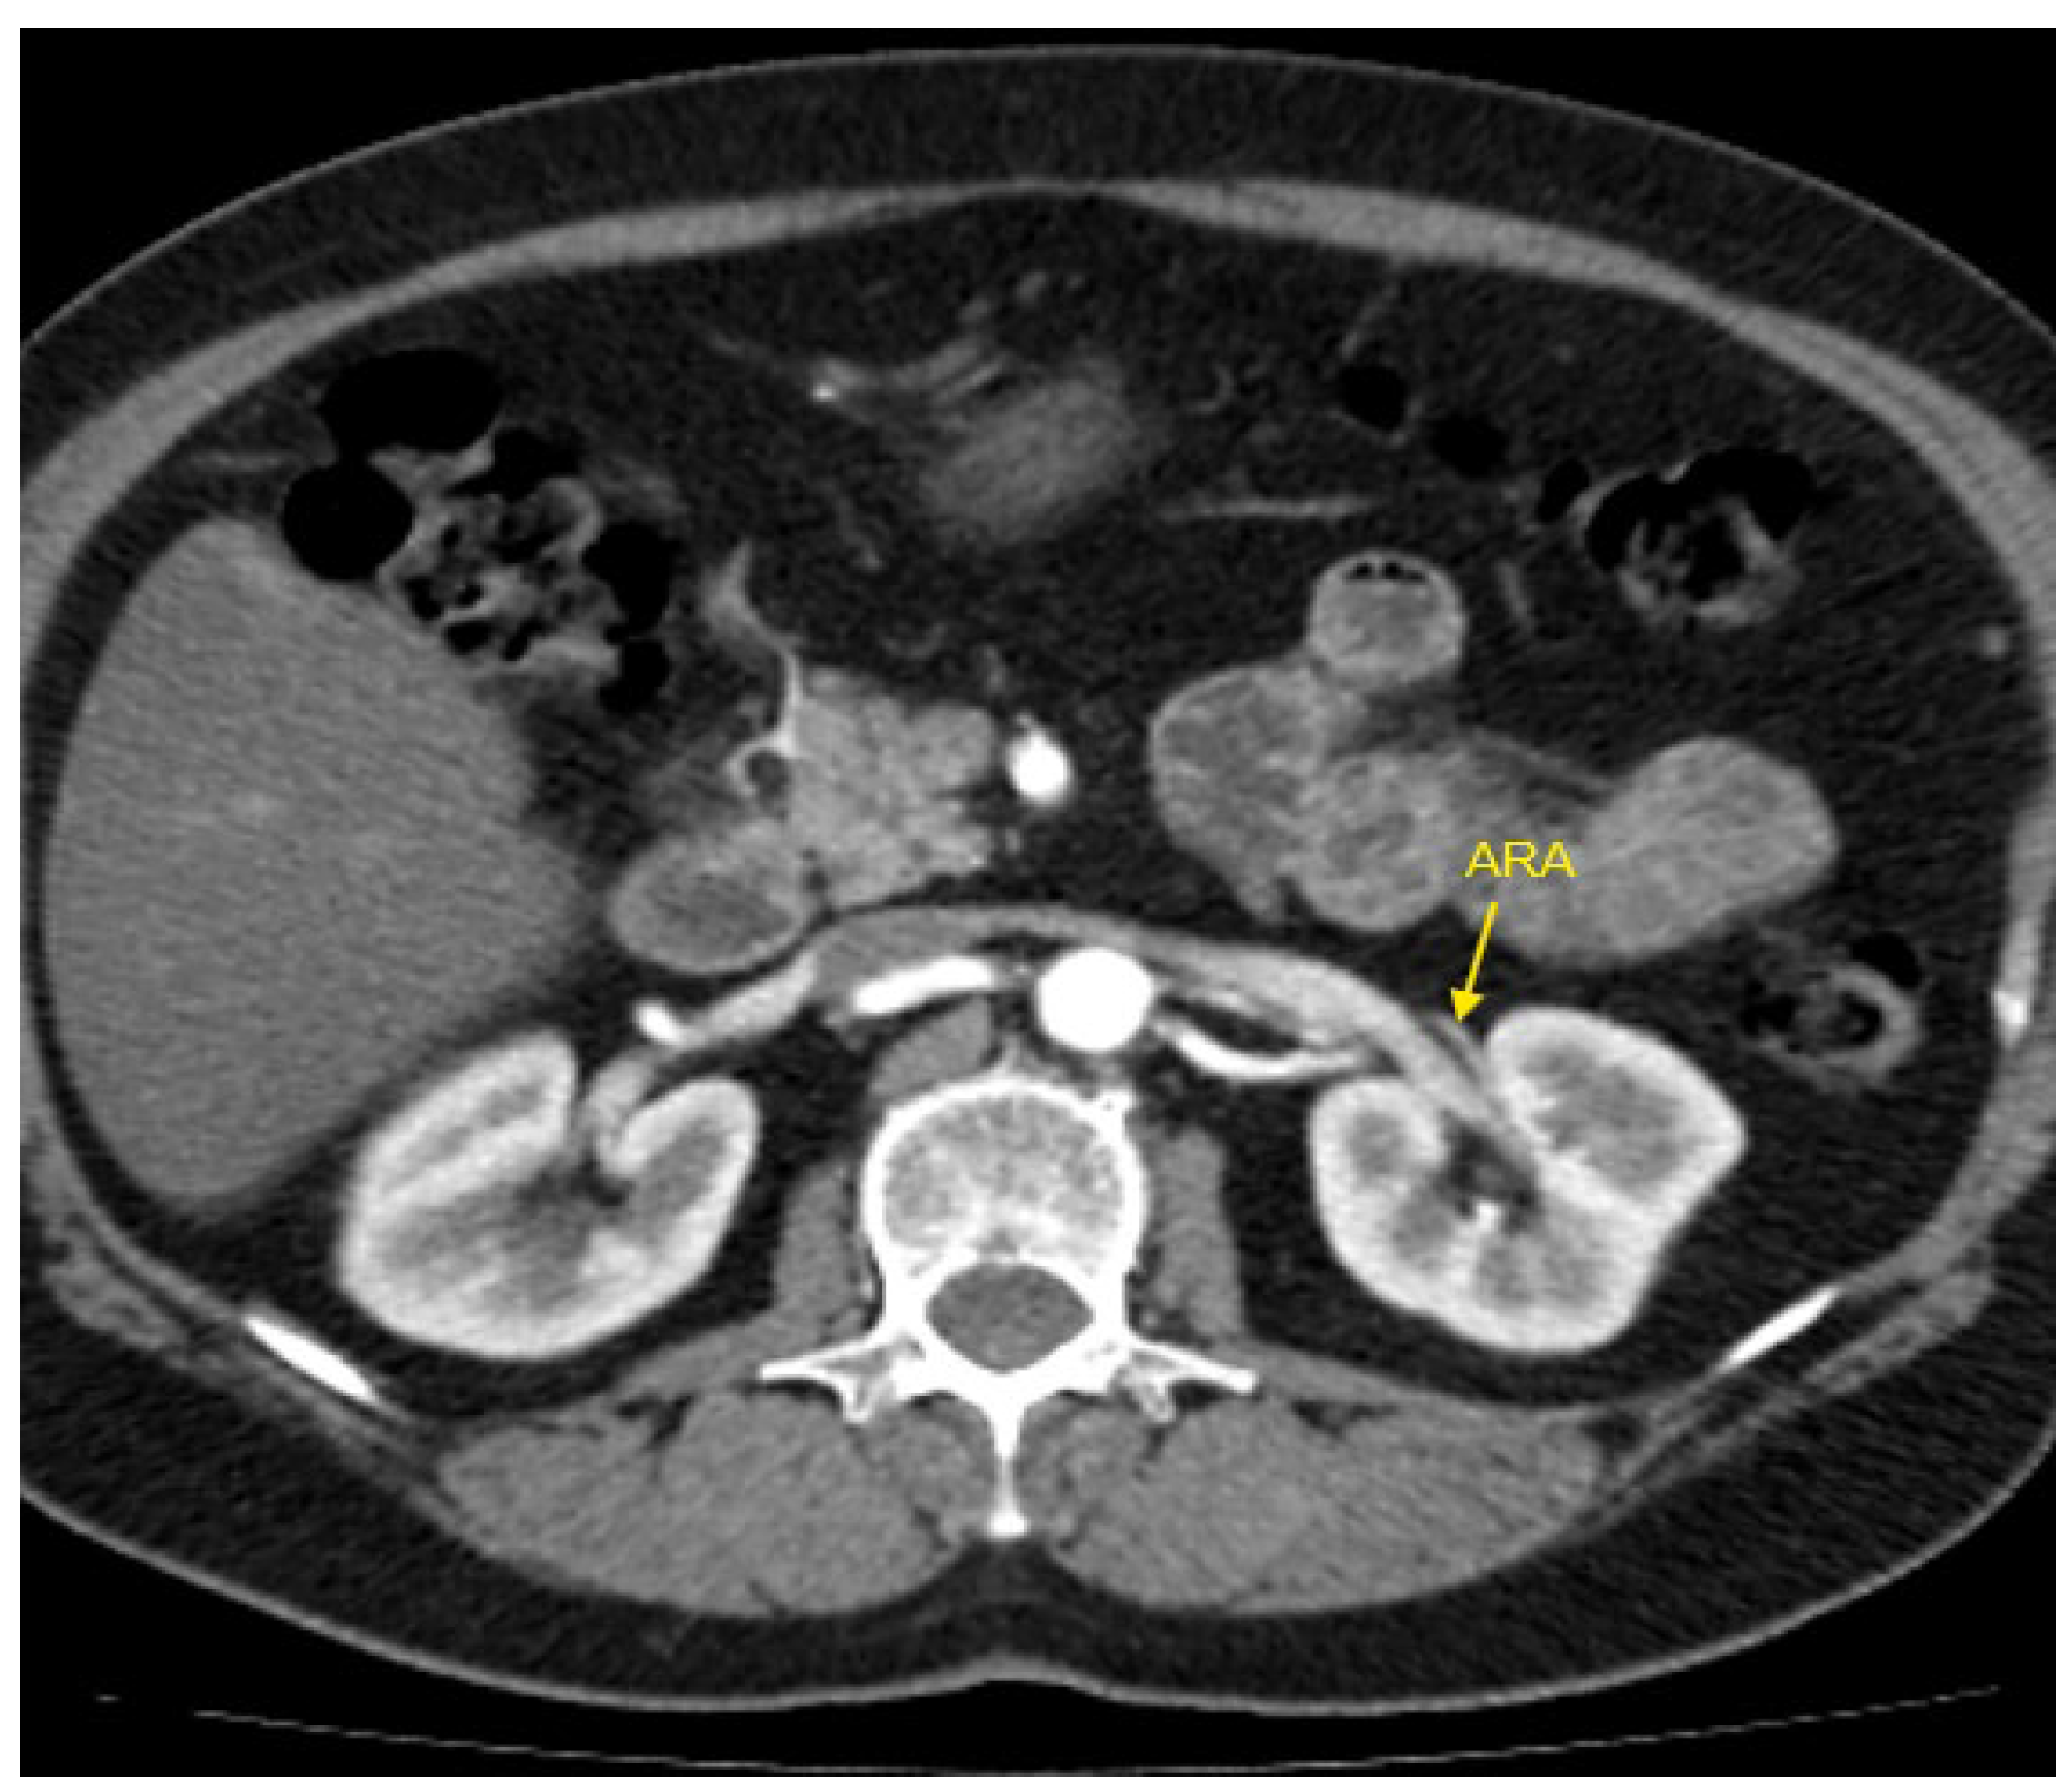

Figure 1, Figure 2, Figure 3, Figure 4 and Figure 5 show examples of some renal vascular abnormalities we identified in our study population.

Figure 2. Contrast-enhanced CT imaging of a 47-year-old female patient with refractory hypertension revealed an accessory renal artery in the left kidney, shown by the yellow arrow. ARA—accessory renal artery; CT—computed tomography.